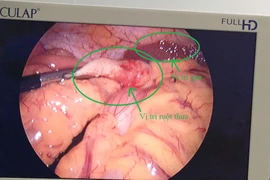

Chủ quan với đau bụng, tưởng rối loại tiêu hóa, bệnh nhân đã bị viêm phúc mạc, áp xe ruột thừa. Tỷ lệ tử vong do viêm phúc mạc ruột thừa chiếm 60 – 70% nếu không được cấp cứu kịp thời.